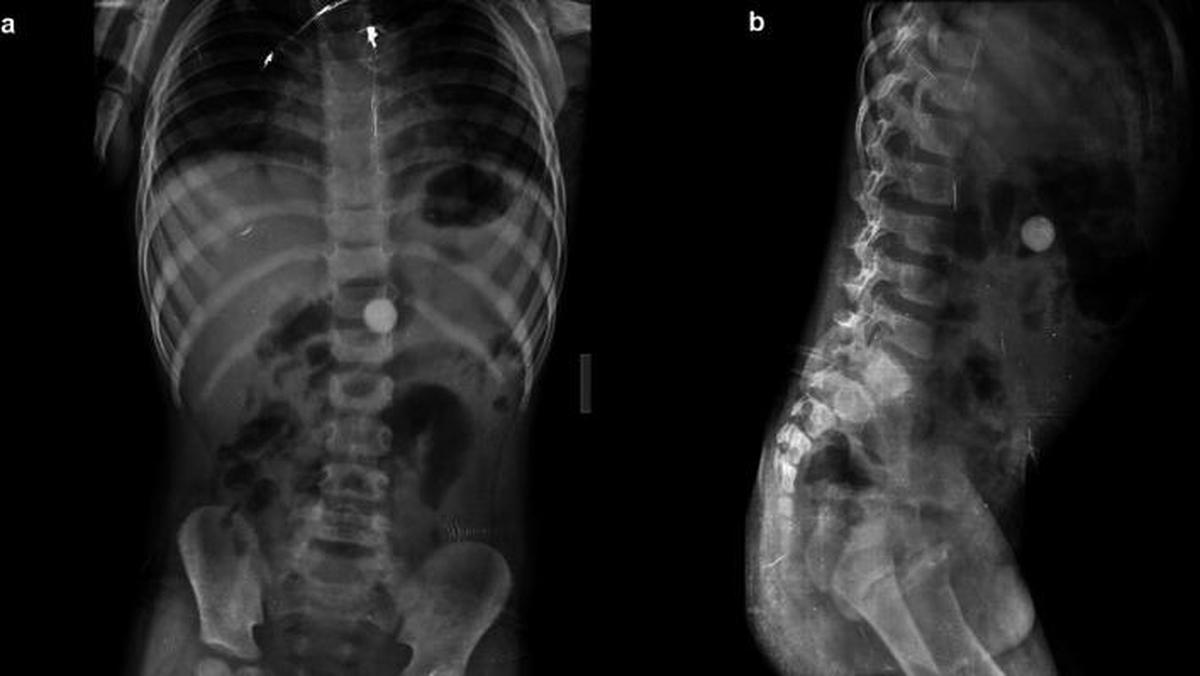

Jakarta – Melewati pemeriksaan rontgen, Ahli Kebugaran seringkali menemukan kejadian medis aneh hingga temuan benda-benda Foreign Di tubuh manusia. Ini beberapa Hingga antaranya.

Artikel ini disadur –> Detik.com Indonesia Berita News: Foto-foto Rontgen Temuan Benda Aneh Di Tubuh, Alat hingga Kawat Besi